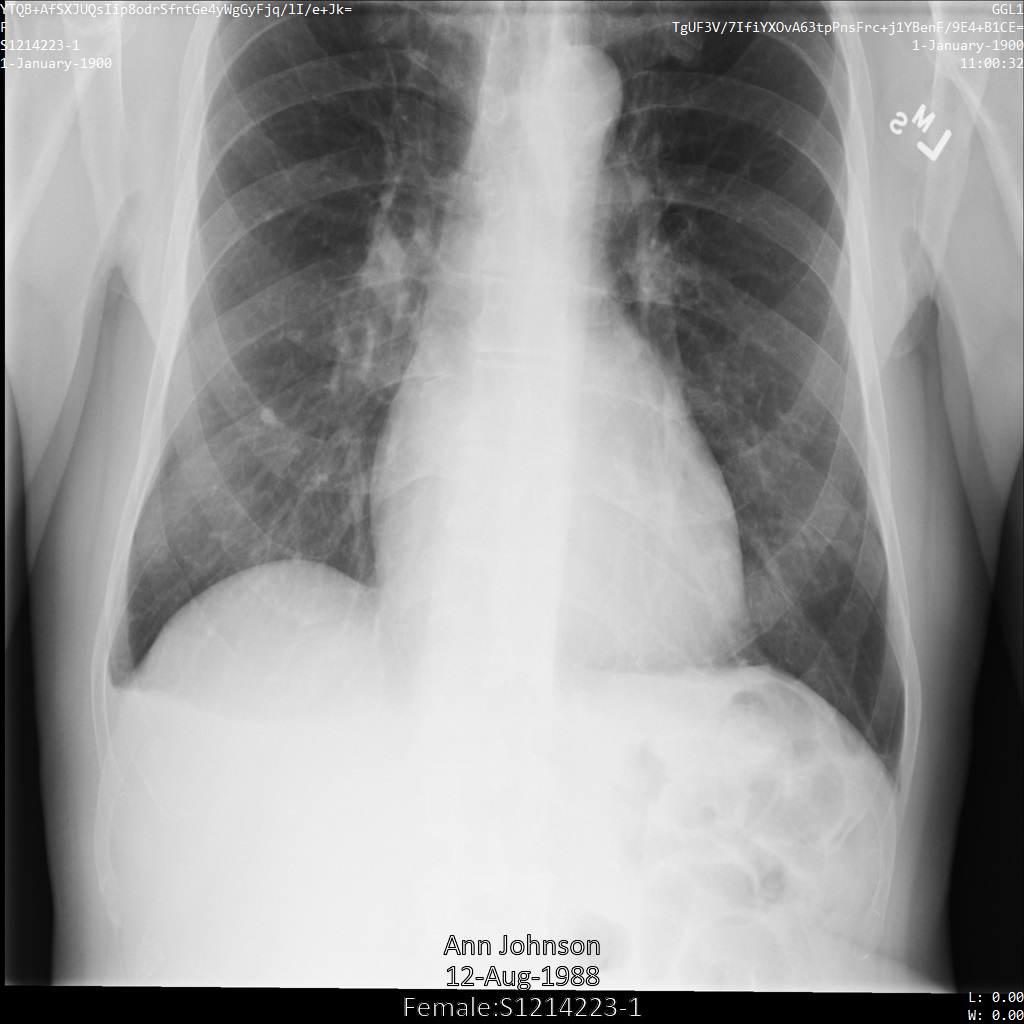

다음 이미지는 환자의 수정되지 않은 x-레이를 보여줍니다.

REDACT_SENSITIVE_TEXT 옵션을 사용하여 Cloud Healthcare API에 이미지를 제출하면 이미지가 다음과 같이 표시됩니다.

다음과 같은 상황을 확인할 수 있습니다.

- 이미지 왼쪽 하단의

PERSON_NAME이 수정되었습니다. - 이미지 왼쪽 하단의

DATE이 수정되었습니다.

기본 DICOM infoType에 따라 민감한 텍스트로 간주되지 않으므로 환자 성별이 수정되지 않았습니다.